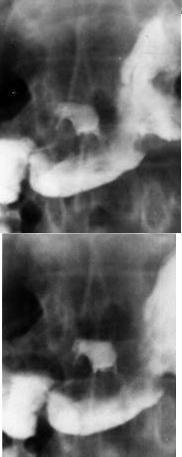

Gastrite a Helicobacter pylori : Diagnostic se base

sur test respiratoire et serologique ,endoscopie et la TOGD

++ double de contrast baryte . Image de epaissisement

des plies gastrique est le meilleur crictere de diagnostic

radiologique .

Image radiologique TOGD de

l'estoma et duodenale avec epaisissement des plies

muqueuses gastriques d'une gastrite a

helicobacter pylorie . |

Image

radiologique TOGD et double de contrast d'une

gastrite Helicobacter pylori , stade avance et

chronique |

Gastrite chronique a Helicobacter pylori |